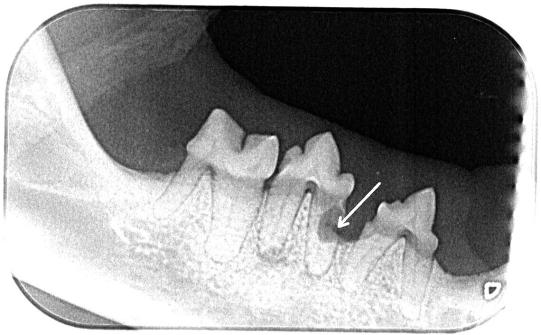

Im Röntgen ist ersichtlich, dass auch der davor liegende Zahn betroffen ist. Nachdem die betroffenen Zähne gezogen wurden, wird der Abszess ausgiebig gespült und eine Drainage eingelegt.

Nun werden auch die restlichen Zähne der Katze untersucht und Zahnröntgen angefertigt. Unterhalb eines Backenzahnes des rechten Unterkiefers ist eine rötliche Schwellung auszumachen. Obwohl die Krone des Zahnes intakt erscheint, zeigt das Zahnröntgen, dass im Wurzelbereich des Zahnes ebenfalls ein Zahnschaden besteht, welcher Knochen und Wurzel auflöst. Auch der davor liegende Zahn ist vom folgenden Knochenschwund betroffen. Die betroffenen Zähne werden ebenfalls entfernt.